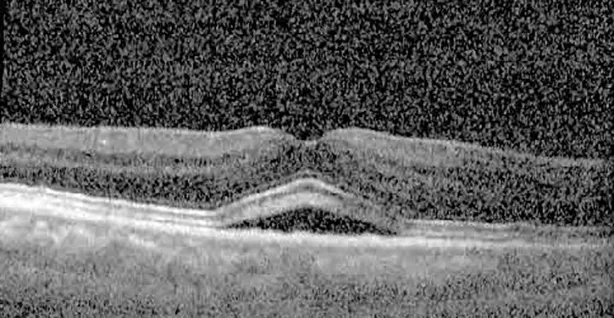

The patient began treatment with oral pemigatinib daily and was followed up for an ophthalmic examination during the second treatment cycle approximately 5 weeks into the treatment process. The patient had at this stage received 28 doses of 13.5 mg per day, which was administered in cycles of 14 on-days and 7 off-days, and had no visual or ophthalmic complaints. The non-corrected VA was OD 20/30 + 1 and OS 20/20. The OCT examinations revealed subfoveal SRF bilaterally. The fundus examination was otherwise unremarkable outside the patient’s prior documented peripheral drusen. Repeat autofluorescence was overall unchanged, though a slight hypofluorescent ring may be visualized in Figure 2. The current pemigatinib protocol recommendation for asymptomatic patients suggests no dose modification; however, with worsening presentation or positive symptoms, it is recommended to withhold pemigatinib. After discussion with the patient’s oncologist, it was decided to continue the medication at this time. Serial monitoring of the patient’s symptoms, vision, and SRF were conducted on specific days during active treatment cycles and days off-cycle to monitor the SRF. Subsequent evaluations demonstrated complete resolution of SRF while off-cycle, and asymptomatic re-accumulation of fluid while on-cycle with varying levels of VA. (Table 1) As we see demonstrated in the table below, in the later stages of the active cycles, such as day 13 of 14 of cycle 2, day 13 of 14 of cycle 3, day 13 of 14 of cycle 4, and day 14 of 14 on cycle 5, the patient’s VA showed no correlative changes based on the presence of SRF. The fluctuations in the patient’s VA certainly occurred, but were likely to be secondary to surface changes, as certain off-cycle days actually presented with lower acuities than days when the SRF was present on OCT examination.

Table 1

| Cycle, day, on/off | VA OD; OS | CMT OD; OS | OCT OD | OCT OS |

| Cycle 2, day 13/14, on | 20/30+1; 20/20 | 365; 355 | ![]() | ![]() |

Highlights the visual acuity, central macular thickness, and the physical OCT of the macula for this patient in both the right and left eyes during various stages of the patient's chemotherapy treatment cycle.